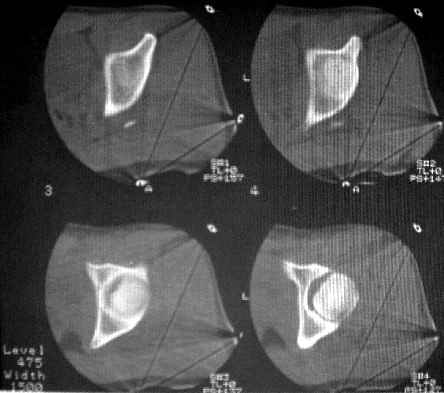

Уважаемые коллеги! Спасибо всем, кто откликнулся на обсуждение. На сегодня доделаны боковые снимки и КТ. Компьютера с возможностью 3D реконструкции на Камчатке нет. Официальное заключение по имеющимся сканам: имеется оскольчатый перелом головки бедра с фрагментацией ее передне-нижнего отдела. Соотношения в суставе в настоящее время правильные. Кзади и выше него в мягких тканях - отдельно лежащий костный фрагмент 15х25 мм (вероятно от головки).

Досылаю на форум КТ и R-граммы. У самого, откровенно говоря, сомнения остаются относительно того, что это не фрагменты вертлужной впадины. В последнем случае, думаю надо оперировать, а если это фрагменты головки из ненагруженной зоны - то не уверен. Какие есть мнения, в том числе и по срокам рагрузки сустава? Главный травматолог Камчатского Военно-морского госпиталя Булахтин Юрий Алексеевич Больного сейчас ничего не беспокоит. Уложен на щит, иммобилизация деротационным сапогом.

КТ1

КТ2

КТ3

Под 65 градусов

Аксиальный головки